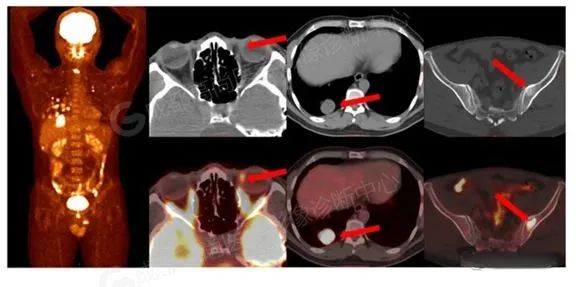

全身转移期:多为血行转移,常见于肝脏、皮下组织、中枢神经系统、肺、胃、骨髓等。

PET/CT 可显示肿瘤位置、大小、眼眶内浸润范围及有无远处转移,是判断预后的重要影像学方法 [4-5]。张蕾等发现 18 F-FDG PET/CT 对高危型 CM 的检出率明显高于低危型,提示 18 F—FDG 摄取可能与组织病理学分型有关,18F—FDG PET/CT 或有助于评估 CM 患者预后。FINGER 等 [7] 认为标准摄取值升高是 CM 转移的危险因素,PET/CT 有助于评估 CM 转移潜能。评价细胞分型及跟踪随访、研发用于 诊断 CM 的特异性核素显像剂均可作为下一步研究方向 [8]。

18F-FDG PET/CT 显示眼球内病变的分辨率虽不及超声、磁共振, 但 PET/CT 可以发现或排除其他部位的原发肿瘤或转移病灶,在判断眼部占位性质及脉络膜黑色素瘤 TNM 分期上作用显著,可发现其他部位的原发恶性肿瘤或脉络膜黑色素瘤的转移灶,进而更好的协助临床进行诊断、分期及预后评估等工作。